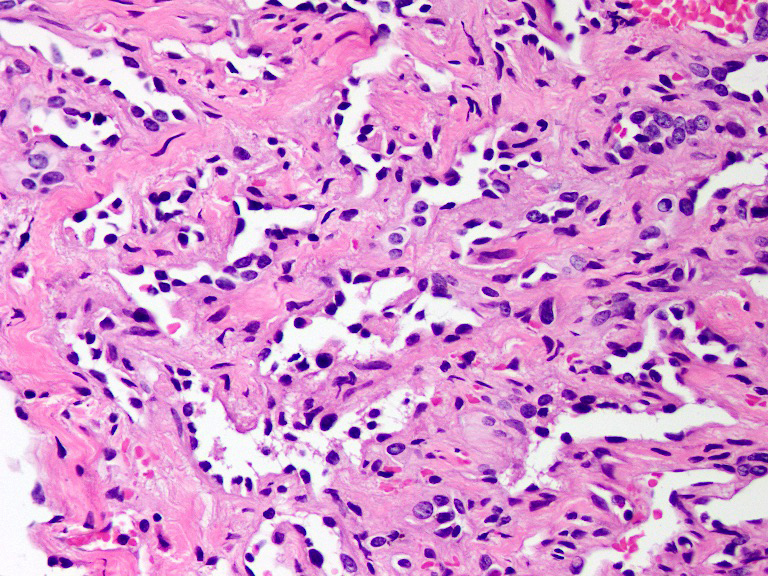

Microscopic (histologic) description

- Poorly circumscribed lesion, infiltrating dermis and subcutis with dissecting planes (Int J Clin Exp Pathol 2010;3:528)

- Composed of elongated arborizing vascular channels that resemble rete testis, hence the name

- Endothelial cells are bland with hobnailed hyperchromatic nuclei

- Nuclear atypia is not seen

- Mitotic figures are rare

- Lesional stroma is fibrotic and shows lymphoid infiltrate (J Med Case Rep 2021;15:69, Int J Clin Exp Pathol 2010;3:528)

- Occasional solid growth may be seen (Stockman: Diagnostic Pathology - Vascular, 1st Edition, 2015)

- In the dermis, vessels may become ectatic and lose retiform appearance

- Occasional cells with cytoplasmic lumina may be rarely seen (J Med Case Rep 2021;15:69)

- Occasionally, intraluminal papillary proliferation may be seen, resembling Dabska tumor (Hornick: Practical Soft Tissue Pathology - A Diagnostic Approach, 2nd Edition, 2018)

Microscopic (histologic) images

A 30 year old man presents with a red to purple plaque involving the right thigh. A punch biopsy through the lesion shows light microscopic features as depicted in the photomicrograph above. Which of the following is the most likely diagnosis in this case?

E. Retiform hemangioendothelioma. The photomicrograph shows a vascular lesion with retiform vessels lined by a single layer of endothelial cells with hobnailing. A lymphoid aggregate is also present. Answers B - D are incorrect because other characteristic essential features of any of the given options, except atypical vascular lesion, are not seen here. Answer A is incorrect because the clinical scenario is not appropriate for a diagnosis of atypical vascular lesion. Therefore, the correct diagnosis is retiform hemangioendothelioma.